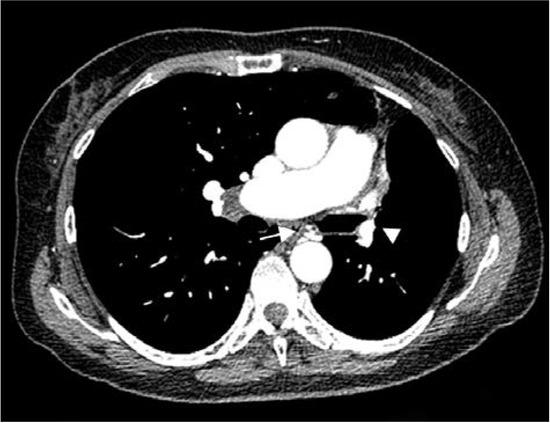

Chest radiography showed slight mediastinum shift to the left, pleuropericardial adhesion on the left, sequelae of TB with no signs of acute infection (Figure 1).

Figure 1. Chest X-ray showing slight mediastinum shift to the left, pleuropericardial adhesion on the left, diminished left hilum, hyperlucent left lung.

Chest X-ray shows diminished ipsilateral hemithorax with hyperlucent lung. Ipsilateral hemidiaphragm is elevated and the mediastinum is shifted to the affected side with insufficient or missing hilum and hyperinflation of collateral lung [6,7].